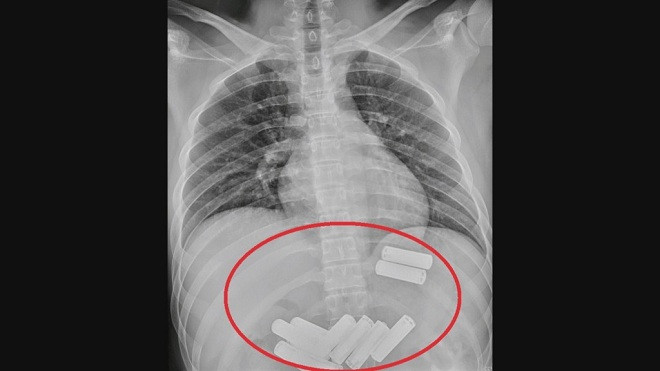

Theo hãng tin CNA, bệnh nhân họ Lee (23 tuổi) sống ở huyện Miêu Lật, phía tây Đài Loan (Trung Quốc) đã cố ý nuốt 11 cục pin vào bụng. Đầu tuần này, Lee được người bạn đưa đến bệnh viện cấp cứu do bị đau bụng dữ dội.

Hình ảnh chụp X-quang cho thấy, trong dạ dày Lee có 11 viên pin AA. Bác sĩ Lin Te-fu tại Khoa Tiêu hóa và Gan mật thuộc Bệnh viện Đa Khoa Da Chien cho hay, phần lớn các ca nuốt phải dị vật xảy ra ở trẻ em. Tuy nhiên, người trưởng thành cũng có nguy cơ nuốt dị vật, nếu họ say rượu.

Ông Lin cho hay, khi nội soi dạ dày của Lee, các bác sĩ phát hiện bên trong có nhiều viên pin. Các bác sĩ đã mất khoảng một tiếng để lấy từng cục pin ra khỏi dạ dày. Sau khi trải qua nội soi đau đớn, Lee khẳng định, “tôi sẽ không bao giờ dám làm điều đó thêm một lần nữa".

Bác sĩ Lin cho hay, nếu bệnh nhân nuốt phải các vật sắc nhọn, nam châm, xương cá, hoặc xương gà thì có nguy cơ thủng thực quản rất cao. Nếu dị vật nằm dưới thực quản, bác sĩ cần lấy dị vật ra bằng ống nội soi. Trước khi nội soi, bác sĩ cần chụp X-quang để xác định vị trí dị vật.

Cũng theo ông Lin, không phải tất cả dị vật bị vô tình nuốt phải đều cần nội soi khẩn cấp. Nếu dị vật nhỏ hơn 2cm, nó có thể tự đi qua đường tiêu hóa trong vòng 4 - 6 ngày.